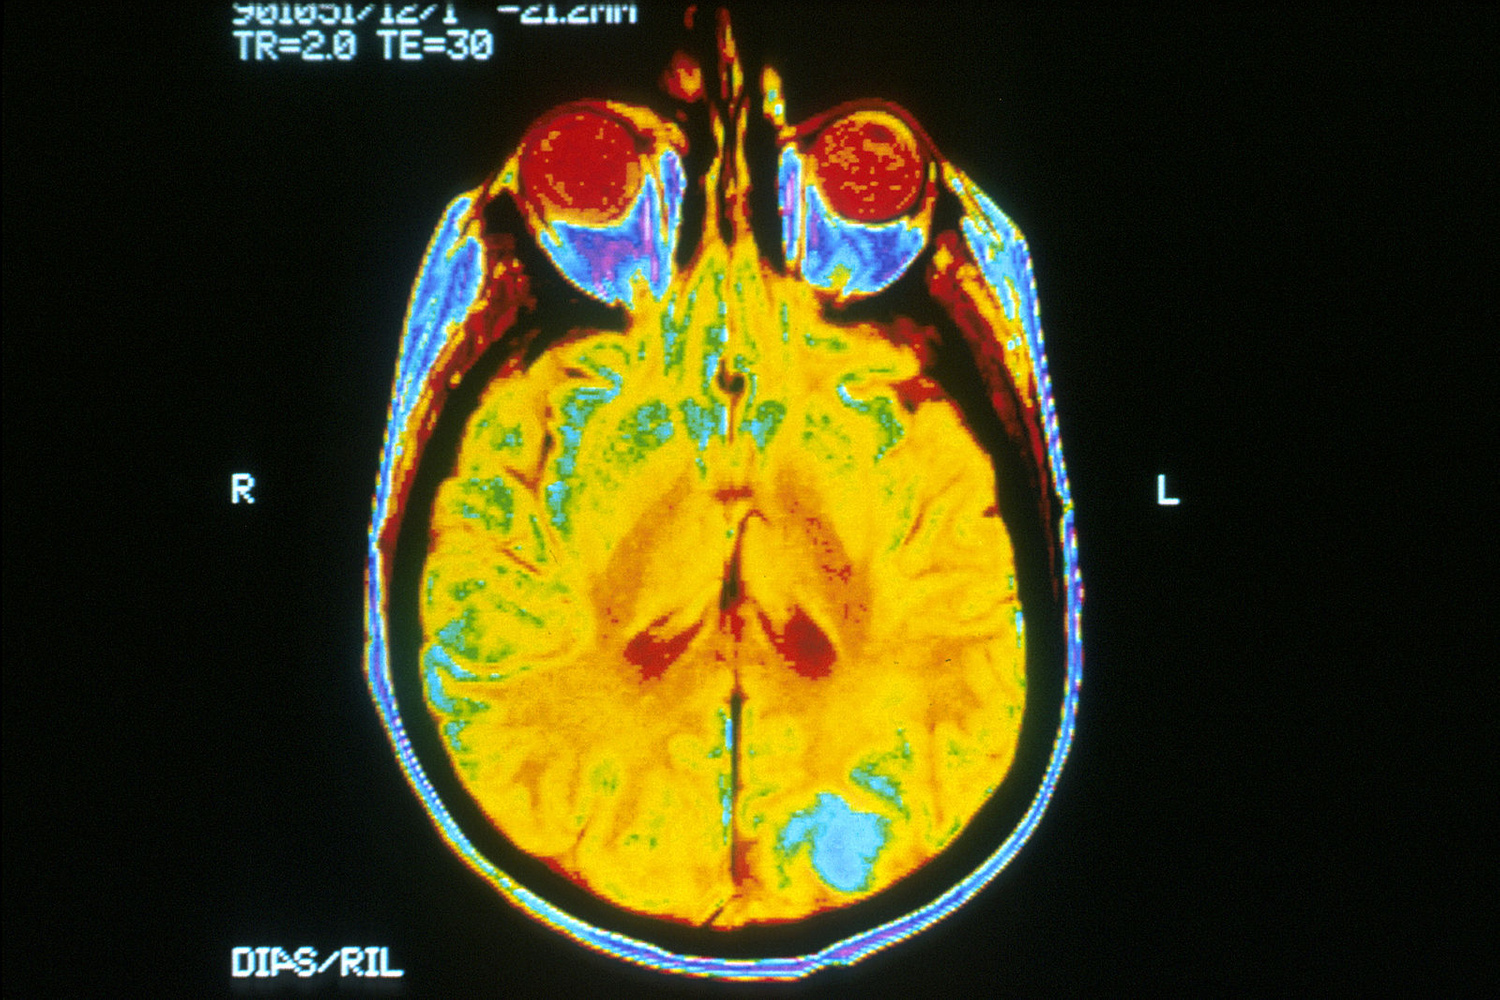

BRAINS retraces the captivating history of neuroimaging—the visualisation of the brain’s structure, function, and biochemical activity—by illustrating the evolution of techniques used to represent the brain over the centuries.

Neuroimaging has significantly advanced from its early beginnings, transforming our ability to diagnose neurological conditions, map brain activity, and guide surgical procedures. From the initial anatomical drawings to today’s high-resolution imaging technologies, the field has made remarkable strides, enabling real-time observation of brain activity and tracking of neural pathways.

Beginning with foundational methods like X-rays and the pioneering use of electroencephalography (EEG), neuroimaging has progressed to sophisticated technologies such as Magnetic Resonance Imaging (MRI) and Positron Emission Tomography (PET). Each technological leap has enhanced our understanding of the brain’s intricate architecture (structure) and its dynamic processes (function), providing deeper insights into the workings of the nervous system.